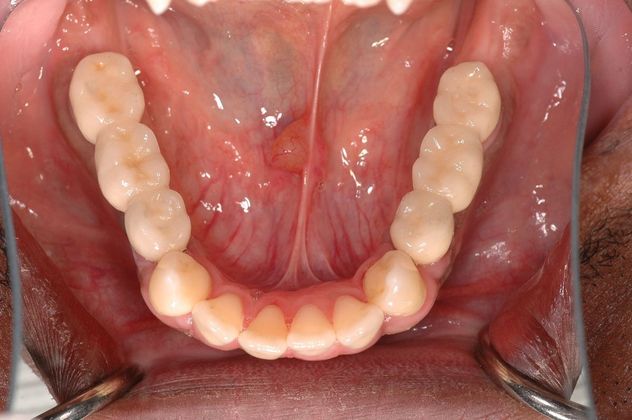

This young man had an early onset of periodontal disease (gum disease) causing him to have all loose upper teeth and loose lower back teeth, all of which needed to be removed. After that, 6 implants were placed in the upper jaw for the All-on-6 bridge and 4 implants were placed in the lower jaw for bridges for back side of the mouth. The lower front natural teeth were cleaned off disease and maintained.

Procedures : extractions, implants, All on 6, Teeth in a day, bite correction.